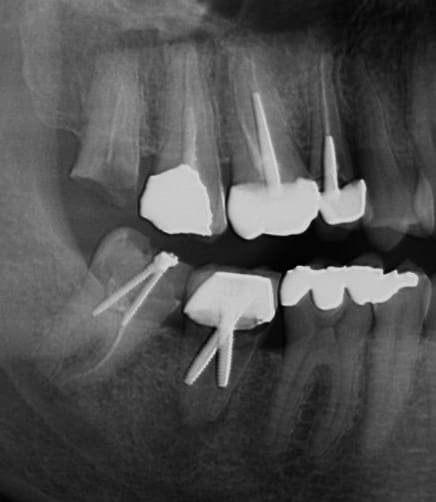

> J'admire la façon ingénieuse et pratique que le praticien a adopté sur la 35

> pour résoudre le problème toujours fastidieux des points de contact. Pas une

> minute n'est perdue avec des matrices, des coins ou tout autre dispositif

> souvent un peu ennuyeux et vieillot.

>

Tu confonds tout...

C'est la technique dite du "club sandwich" :

Tu prends un bout de racine résiduelle (de préférence bien délabrée),

tu rajoutes un peu de ciment onctueux foulé au pouce

puis tu poses par dessus ton petit "bridge 1 dent" en résine => pas besoin de le coller aux dents adjacente, car tu vas transvisser à travers un gros screw post de chez black et decker!

Et voilà ton club sandwich (SC79+Z15) est prêt pour une belle radio obligatoire, mais que personne d'autre que toi ne verra...

Illustration de la pertinence d'un status sur un risque carieux pourtant faible. Réalisé ce matin sur un nouveau patient. Ras à l'examen endo-buccal.

12/03/2014 à 16h34

Fidélisation ou risquer de passer pour un méchant dentiste avide.

Patient qui vient car son plombage sur 28 est tombé.

Faut il repondre à la demande de la patiente en faisant un sc17 en optimisant la nomenclature voir un sc33 puis une couronne alors qu'il y a une jolie féllure qui explique la fuite de la restauration précédente.

ou passer pour un voleur en proposant un implant pour remplacer 26 et faire l'extraction de 28 qui ne demande que cela.

Et le prix de la plus grosse vis est décerné à...

CRUCIFER!

Pourquoi s'embêter à dévitaliser, alors qu'avec une bonne grosse vis dans chaque canal, tu peux à la fois obturer et restaurer ta dent...

60 minutes une endo molaire et 30 minutes pour la reconstituer? Que nenni, 5 minutes suffises! Les tarifs sécu sont encore largement surévalués... :-)